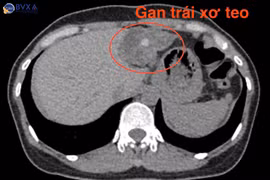

(khoahocdoisong.vn) - Sỏi đường mật trong gan (thường được gọi tắt là sỏi gan), bản chất là sỏi mật nhưng nằm trong các ống gan. Sỏi trong gan thường dễ gây biến chứng hơn so với sỏi tại các vị trí khác trong đường mật.